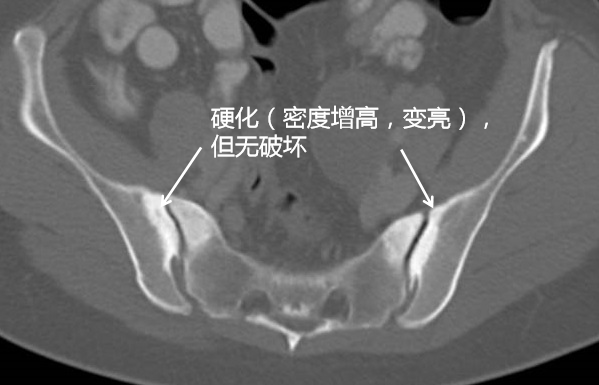

最后诊断为:致密性髂骨炎.